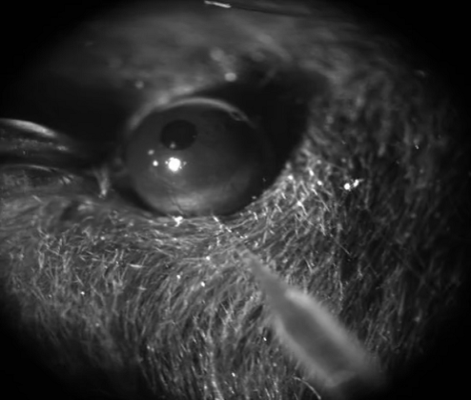

2、眼内注射(玻璃体腔注射)

根据实验需求,将病毒或药物等通过微量注射器注射穿透巩膜脉络膜视网膜,入玻璃体腔,从而达到转染或治疗等目的。玻璃体腔注射可作为研究神经药理和视网膜神经环路的重要技术,利用眼球相对独立的结构,将药物等直接注射在眼球腔体中而减少药物等对其他系统的影响,从而可以实现局部给药。

玻璃体腔注射                                                                     玻璃体腔: AAV-Syn-GcaMP6s